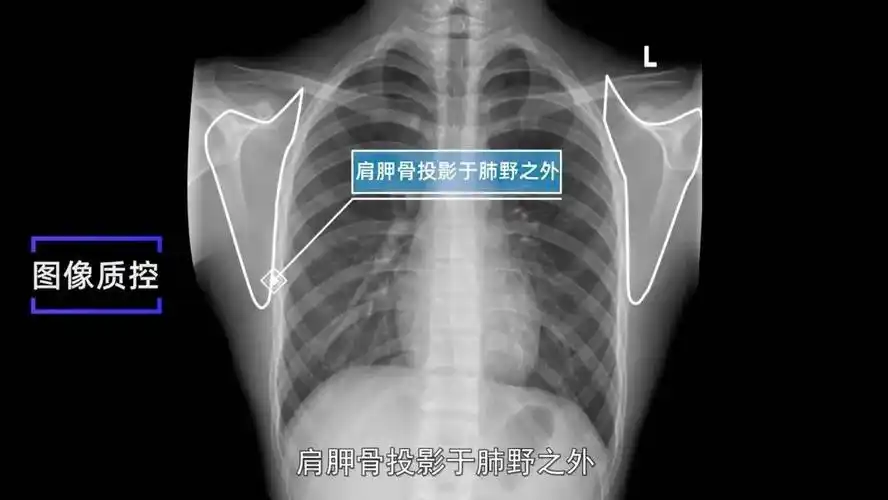

肩胛骨投影于肺野之外.3. 肺尖充分显示.2.

收藏x线摄影技术胸部正侧位摄影标准摆位图文解析